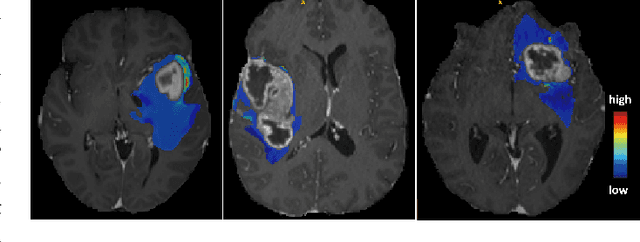

Abstract:AI requires extensive datasets, while medical data is subject to high data protection. Anonymization is essential, but poses a challenge for some regions, such as the head, as identifying structures overlap with regions of clinical interest. Synthetic data offers a potential solution, but studies often lack rigorous evaluation of realism and utility. Therefore, we investigate to what extent synthetic data can replace real data in segmentation tasks. We employed head and neck cancer CT scans and brain glioma MRI scans from two large datasets. Synthetic data were generated using generative adversarial networks and diffusion models. We evaluated the quality of the synthetic data using MAE, MS-SSIM, Radiomics and a Visual Turing Test (VTT) performed by 5 radiologists and their usefulness in segmentation tasks using DSC. Radiomics indicates high fidelity of synthetic MRIs, but fall short in producing highly realistic CT tissue, with correlation coefficient of 0.8784 and 0.5461 for MRI and CT tumors, respectively. DSC results indicate limited utility of synthetic data: tumor segmentation achieved DSC=0.064 on CT and 0.834 on MRI, while bone segmentation a mean DSC=0.841. Relation between DSC and correlation is observed, but is limited by the complexity of the task. VTT results show synthetic CTs' utility, but with limited educational applications. Synthetic data can be used independently for the segmentation task, although limited by the complexity of the structures to segment. Advancing generative models to better tolerate heterogeneous inputs and learn subtle details is essential for enhancing their realism and expanding their application potential.

Abstract:This paper presents the winning solution of task 1 and the third-placed solution of task 3 of the BraTS challenge. The use of automated tools in clinical practice has increased due to the development of more and more sophisticated and reliable algorithms. However, achieving clinical standards and developing tools for real-life scenarios is a major challenge. To this end, BraTS has organised tasks to find the most advanced solutions for specific purposes. In this paper, we propose the use of synthetic data to train state-of-the-art frameworks in order to improve the segmentation of adult gliomas in a post-treatment scenario, and the segmentation of meningioma for radiotherapy planning. Our results suggest that the use of synthetic data leads to more robust algorithms, although the synthetic data generation pipeline is not directly suited to the meningioma task. The code for these tasks is available at https://github.com/ShadowTwin41/BraTS_2023_2024_solutions.

Abstract:This paper presents the second-placed solution for task 8 and the participation solution for task 7 of BraTS 2024. The adoption of automated brain analysis algorithms to support clinical practice is increasing. However, many of these algorithms struggle with the presence of brain lesions or the absence of certain MRI modalities. The alterations in the brain's morphology leads to high variability and thus poor performance of predictive models that were trained only on healthy brains. The lack of information that is usually provided by some of the missing MRI modalities also reduces the reliability of the prediction models trained with all modalities. In order to improve the performance of these models, we propose the use of conditional 3D wavelet diffusion models. The wavelet transform enabled full-resolution image training and prediction on a GPU with 48 GB VRAM, without patching or downsampling, preserving all information for prediction. For the inpainting task of BraTS 2024, the use of a large and variable number of healthy masks and the stability and efficiency of the 3D wavelet diffusion model resulted in 0.007, 22.61 and 0.842 in the validation set and 0.07 , 22.8 and 0.91 in the testing set (MSE, PSNR and SSIM respectively). The code for these tasks is available at https://github.com/ShadowTwin41/BraTS_2023_2024_solutions.